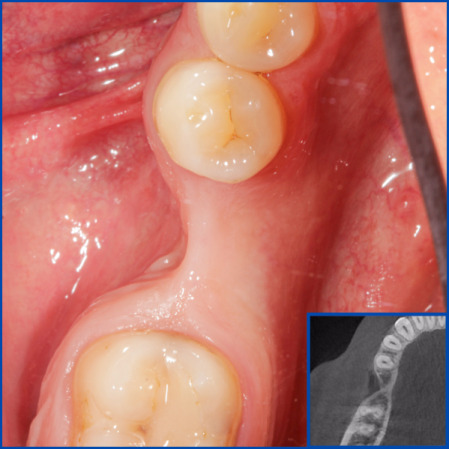

Kist nedeni ile çene kemiğinde defekt oluşmuş vakamıza sert ve yumuşak doku ogmentasyonu uyguladık